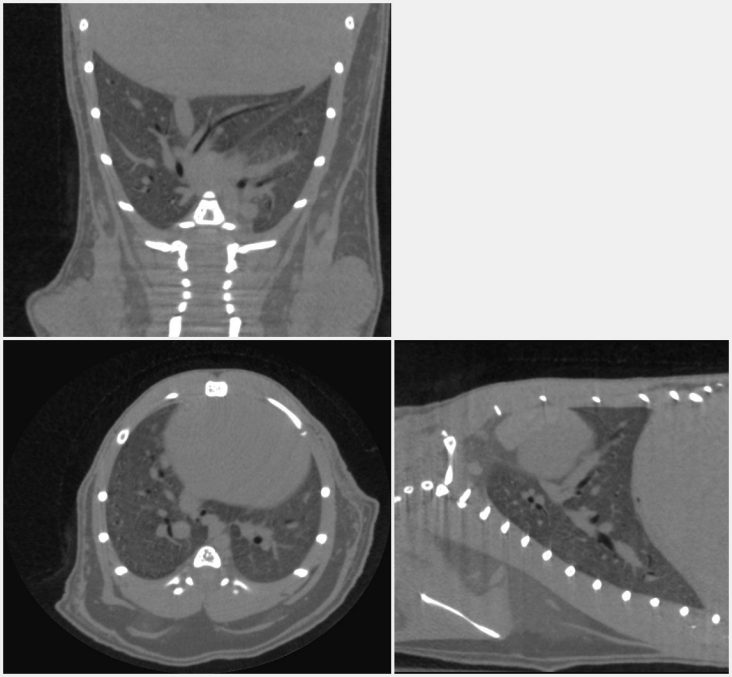

5. Orthogonal cross-sections through the mouse lung scannedin vivo, showing the blood vessels and large airways inside the lung.

5.jpeg